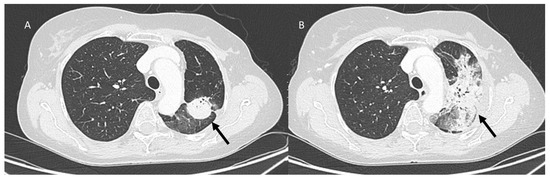

| ICI-related pneumonitis | Diffuse (related to the phase of disease) | Ground-glass and reticular opacities; consolidative opacities; interlobular septal thickening; “crazy-paving” pattern | Autoimmune |

| COVID-19 pneumonia | Diffuse (related to the phase of disease) | Ground-glass opacities; crazy-paving pattern; consolidative opacities; interlobular septal thickening (according to the phase of disease) | Unknown, supposed cytokine storms |